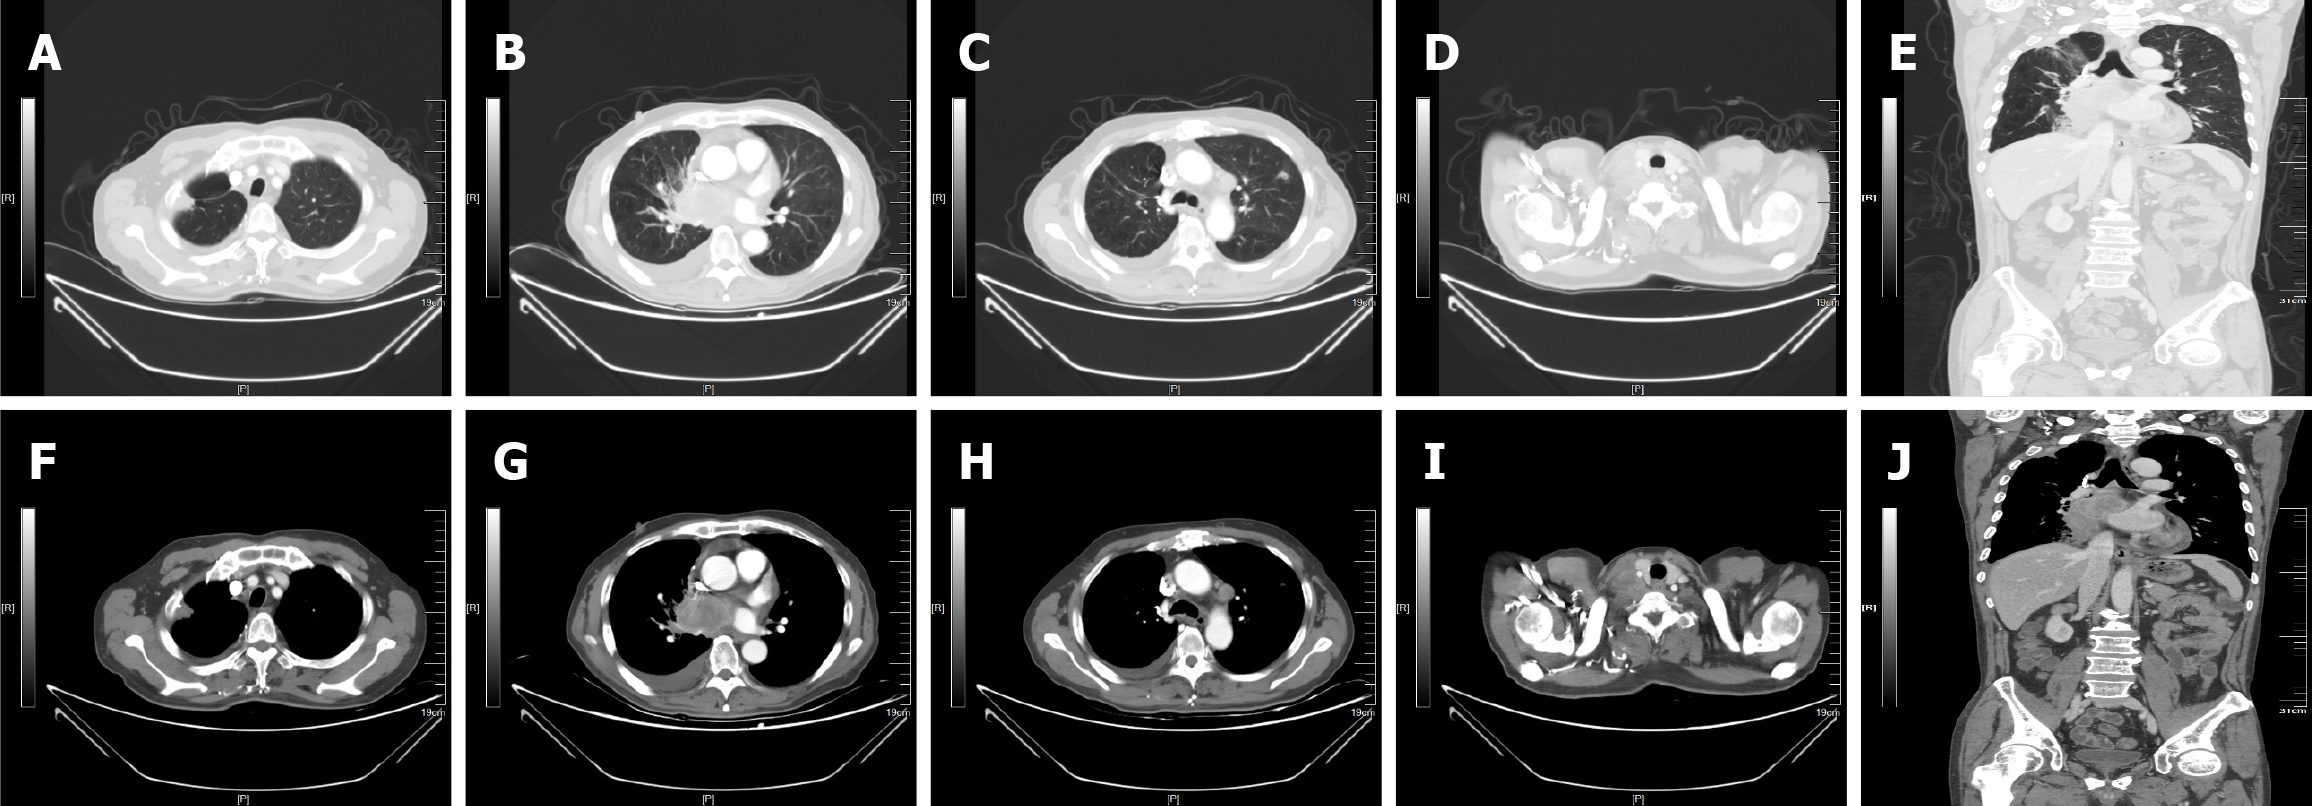

Figure 3 Representative radiologic images of the patient before and after the Kirsten rat sarcoma viral oncogene homolog at glycine 12 to cysteine inhibitor.

A-E: May 31, 2023; F-J: July 25, 2023.